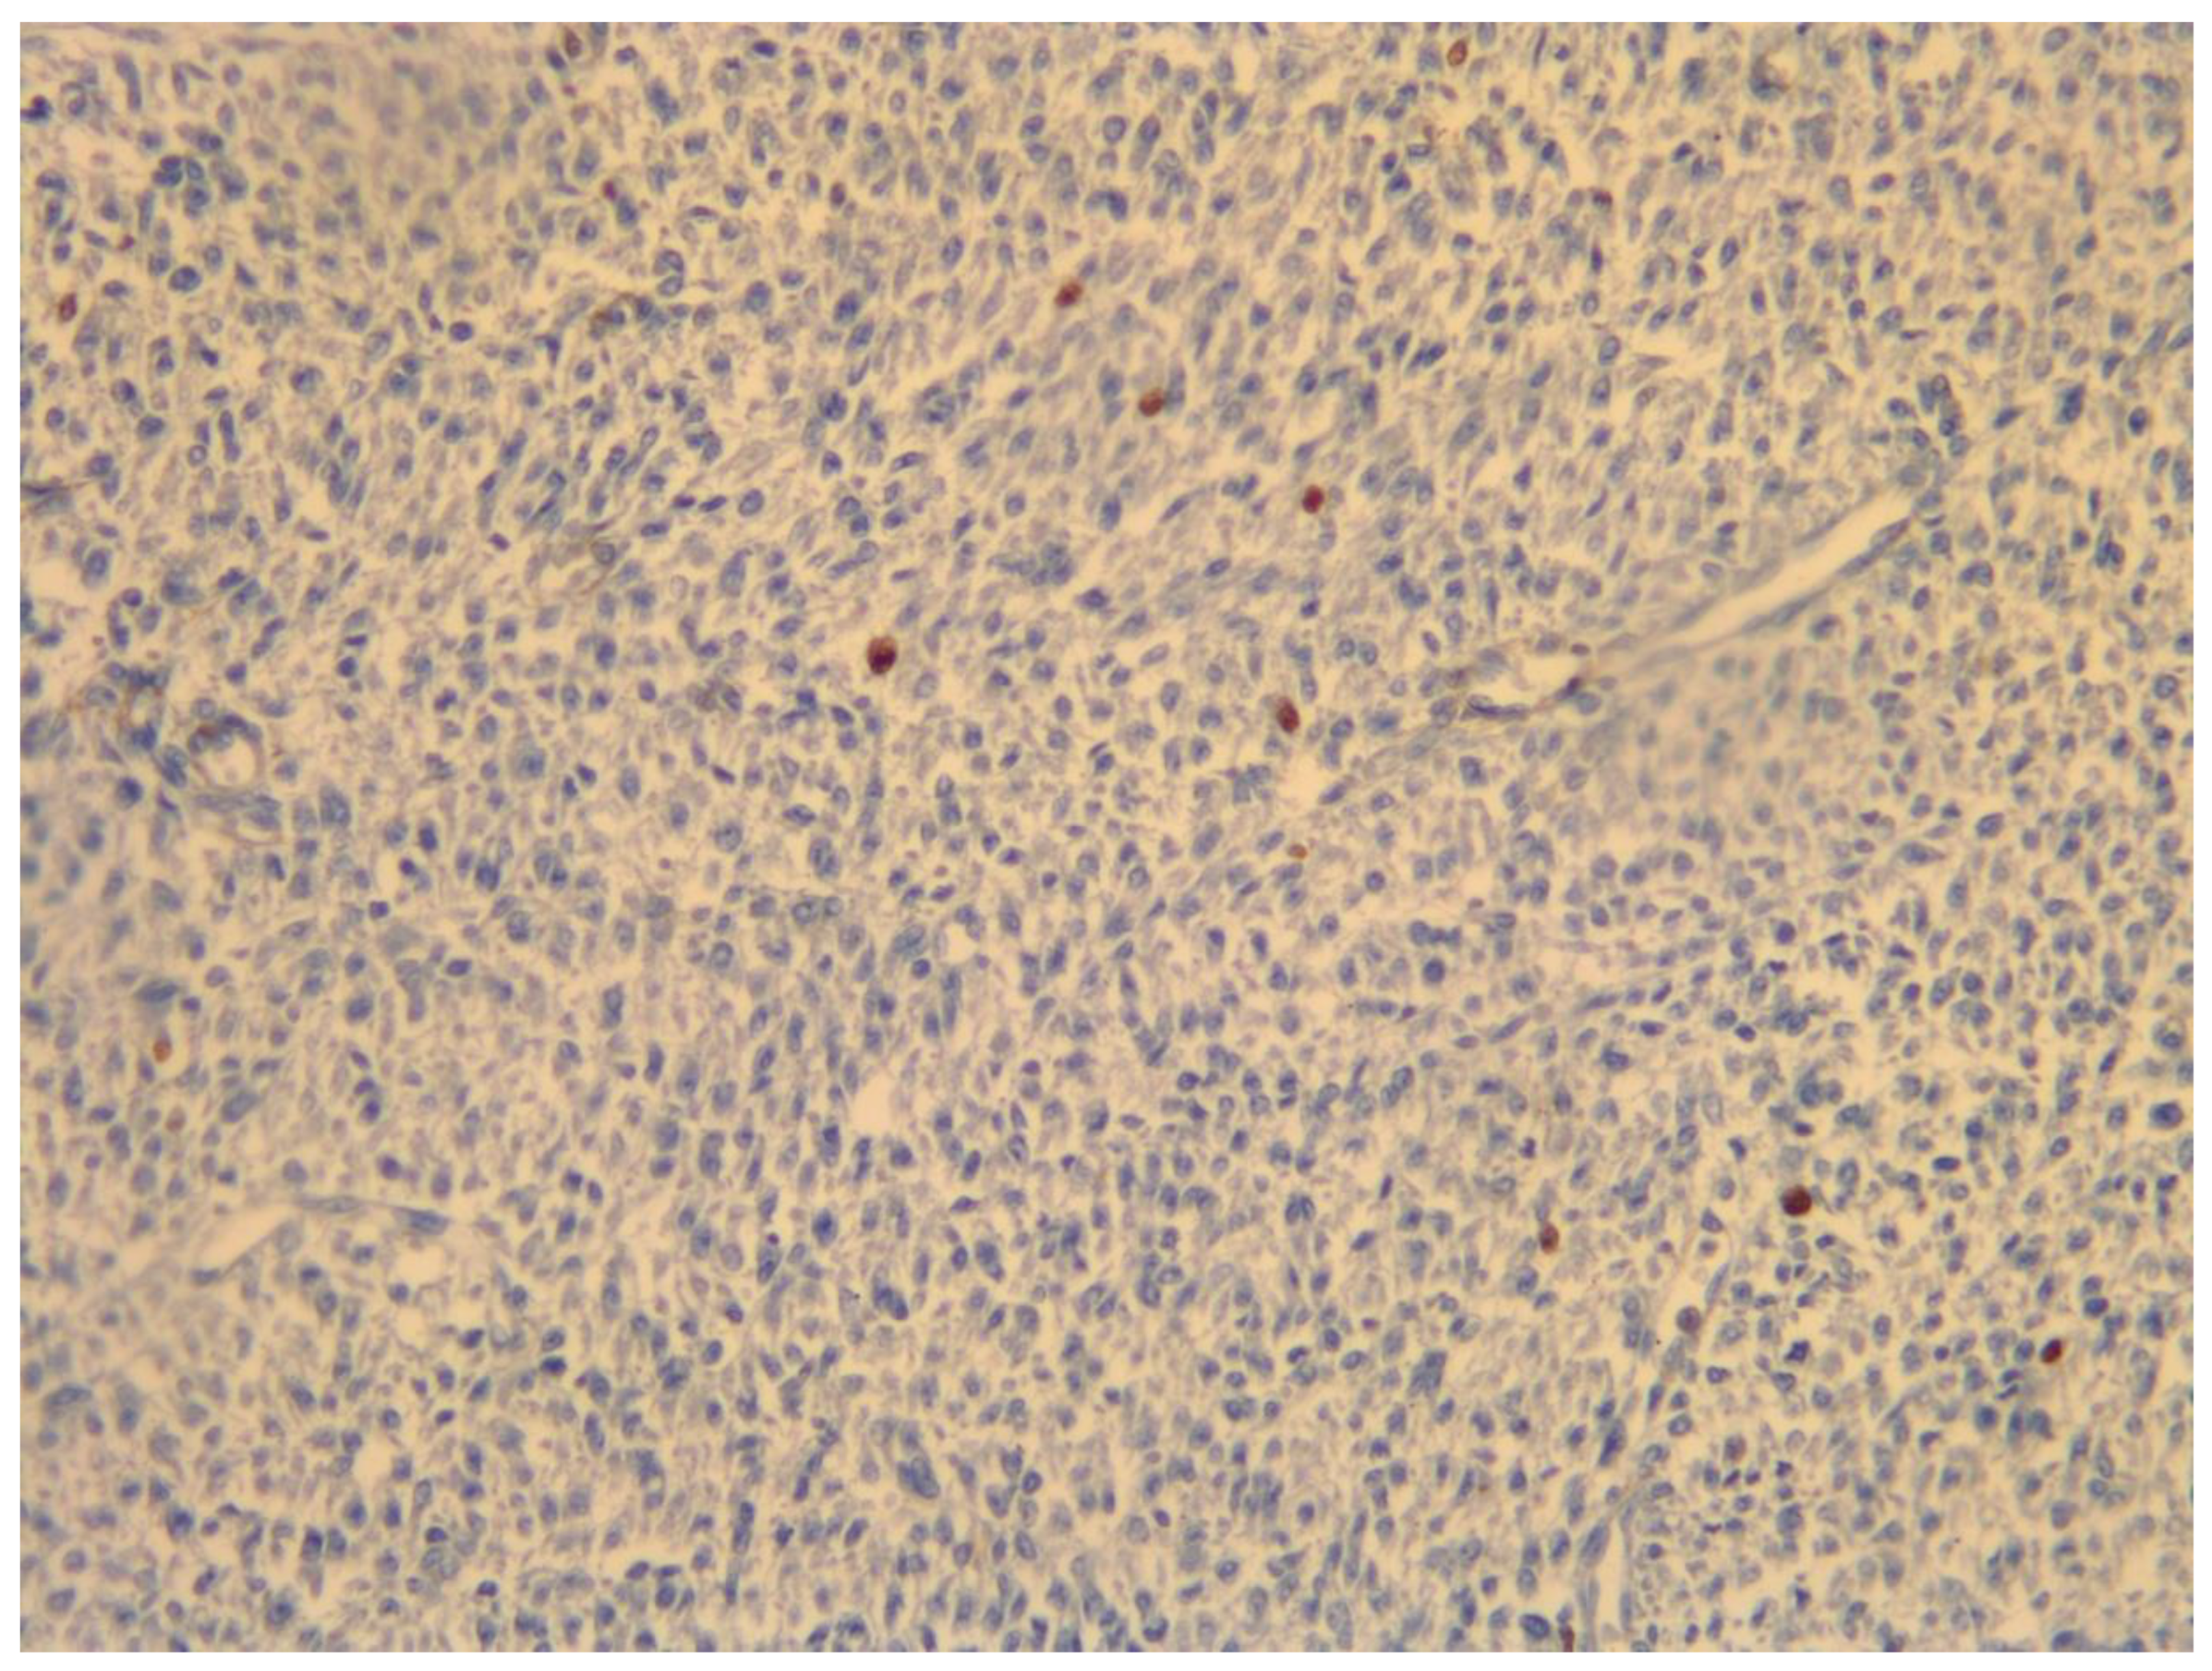

- Travaglino, A.; Raffone, A.; Gencarelli, A.; Neola, D.; Oliviero, D.A.; Alfano, R.; Campanino, M.R.; Cariati, F.; Zullo, F.; Mollo, A.; et al. p53, p16 and ki67 as immunohistochemical prognostic markers in uterine smooth muscle tumors of uncertain malignant potential (STUMP). Pathol. Res. Pract. 2021, 226, 153592. [Google Scholar] [CrossRef]